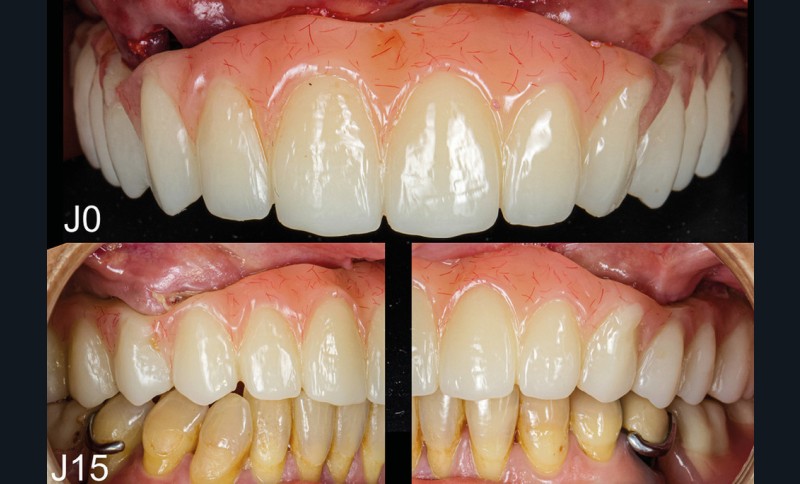

Après une extraction atraumatique des dents résiduelles, nous passons au 3e étage qui est le guide de forage stéréolithographique. La séquence de chirurgie Full guided est passée et les implants ont été torqués entre 40 et 50N.cm2 (fig. 6, 7, 8). Cette stabilité primaire dans les sites d’extraction et des sites greffés a permis la mise en charge immédiate du bridge complet provisoire. Des études cliniques [3, 4, 5] ont montré que la mise en charge immédiate dans les sinus greffés ne pose aucune contre-indication. Le 4e étage est donc celui du bridge provisoire transvissé à l’étage de base et solidarisé en bouche par l’intermédiaire de cylindres provisoires sur piliers MUA, avec une colle duale (GC-LinkForce). L’espace entre les implants et l’alvéole a été comblé par une xénogreffe (Bio-Oss Geistlich). Les profils d’émergence sont travaillés et parfaitement polis. Enfin, le bridge est mis en place, torqué à 20.cm2, équilibré et les consignes postopératoires ont été rappelées à la patiente (fig. 9 et 10).

Notre approche globale dans la gestion de ce cas clinique avec l’aide du flux numérique et l’utilisation des guides à étages nous a permis de traiter cette patiente avec succès, sérénité et de rendre son traitement prévisible.